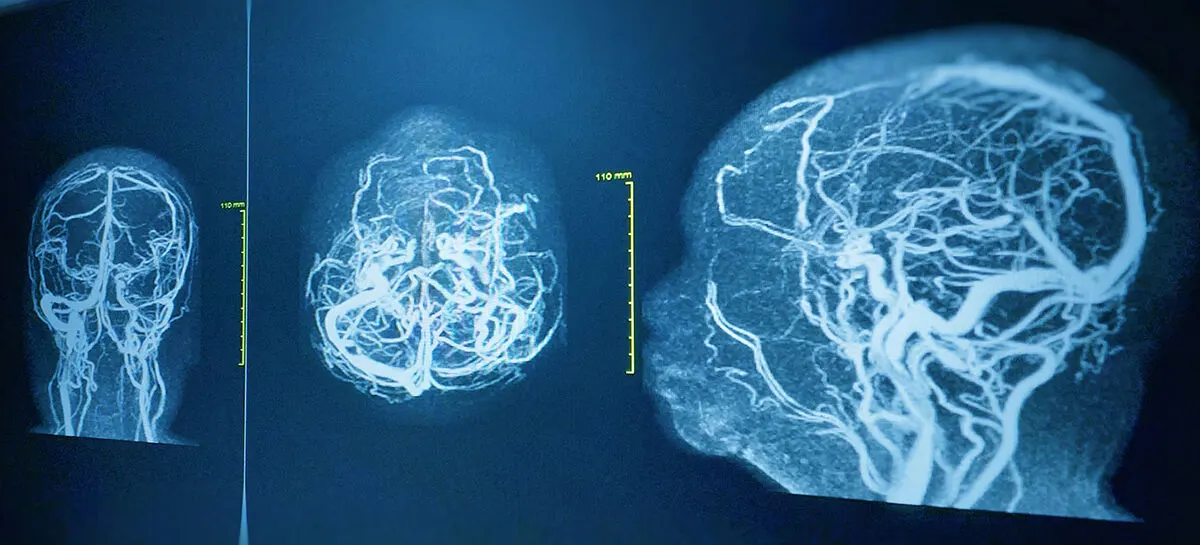

ما هو تصوير الأوعية الدموية في الدماغ ولماذا يتم إجراؤه؟

تصوير الأوعية الدموية في المخ هو إجراء جراحي طفيف التوغل يتم إجراؤه للكشف عن أو تأكيد وجود أي خلل في الأوعية الدموية في المخ أو الرأس أو الرقبة. ويطلق على تصوير الأوعية الدموية أيضًا اسم تصوير الأوعية الدموية أو تصوير الشرايين، ويطلق على تصوير الأوعية الدموية في المخ أيضًا اسم تصوير الأوعية الدموية في المخ…